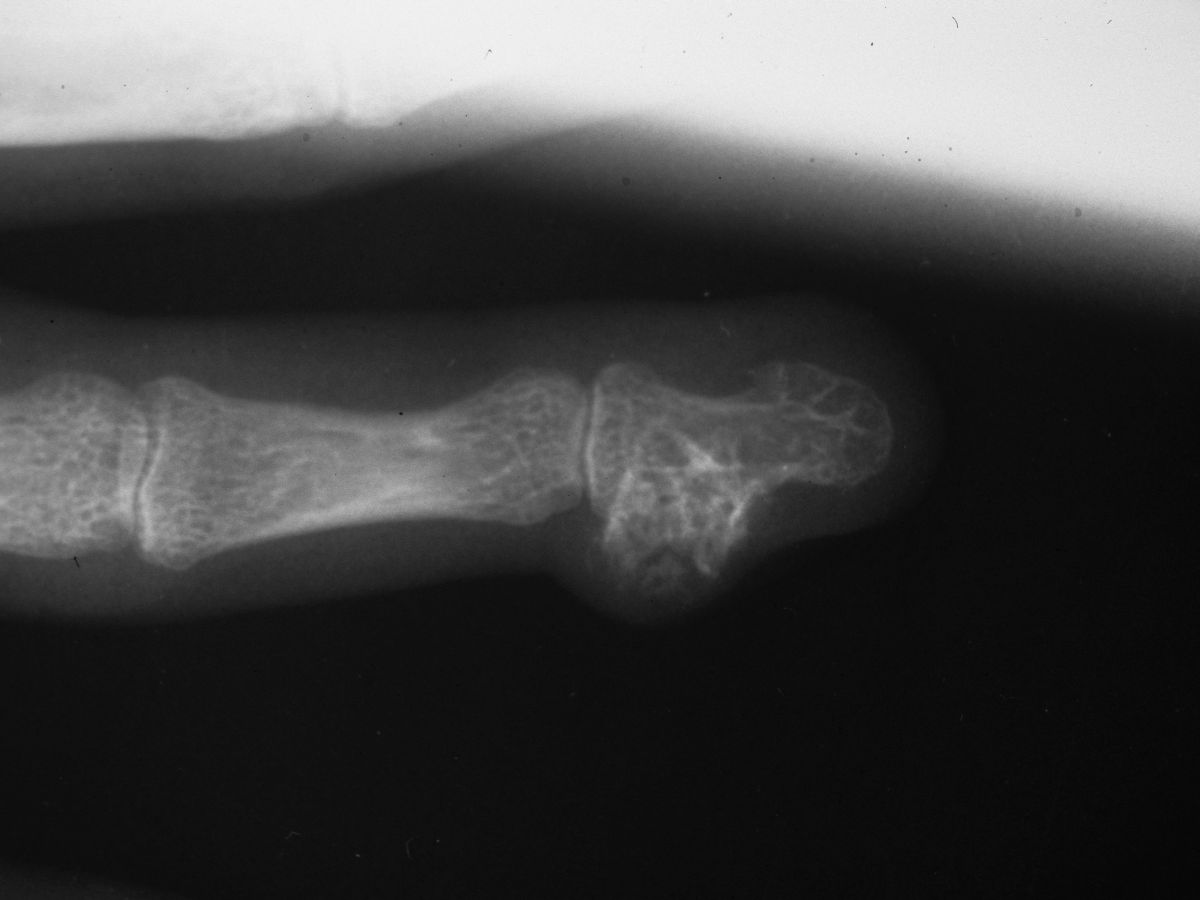

| Case 3. Mass and progressive nail plate contour deformity developed over the last several years in this 42 year old woman. |

| The nail plate is actually folded against itself in an acute angle. |

| On plain radiographs, The mass has a central ossification. The lateral border of the distal phalanx has remodelled with traction exostoses at the attachments of the intraosseous ligament. |